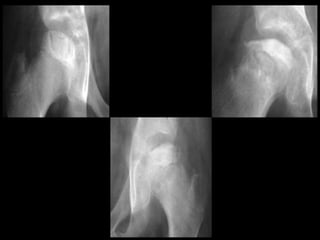

• Bony epiphysis begins to

fragment

• Areas of increased

lucency and density

• Evidence of repair aspects of

disease bony epiphysis begins

to fragment

disease

FRAGMENTATION STAGE:

• Normal bone density returns

• Alterations in shape of femoral

head and neck evident

REOSSIFICATION STAGE